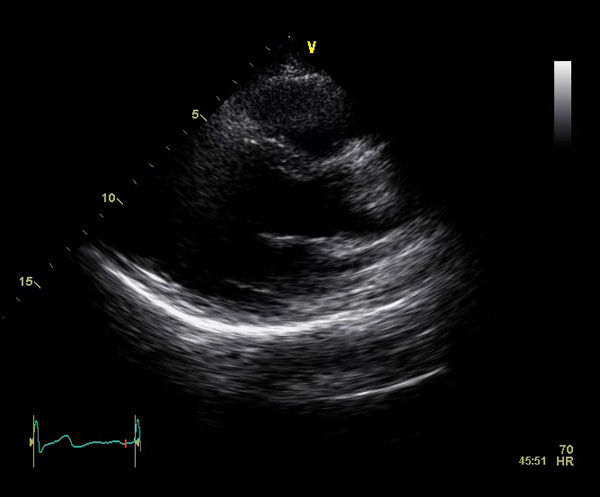

We found out yesterday that I have a hole in my heart. The uncovering of something which can threaten your life makes you face questions which you normally don’t try to answer.

On a normal aorta valve you have three flaps which prevent the blood from leaking back into your heart when it beats. My heart is what they call bicuspid meaning I only have two of the three flaps which leaves a hole; quite a visible hole.

The doctor says that this is congenital, meaning I’ve always had it, I’m only now having some discomfort and other symptoms which caused me to see the cardiologist. From what I’ve read, surgery is the only option to fix this, and the doctor said that I will have a valve replacement in my future.